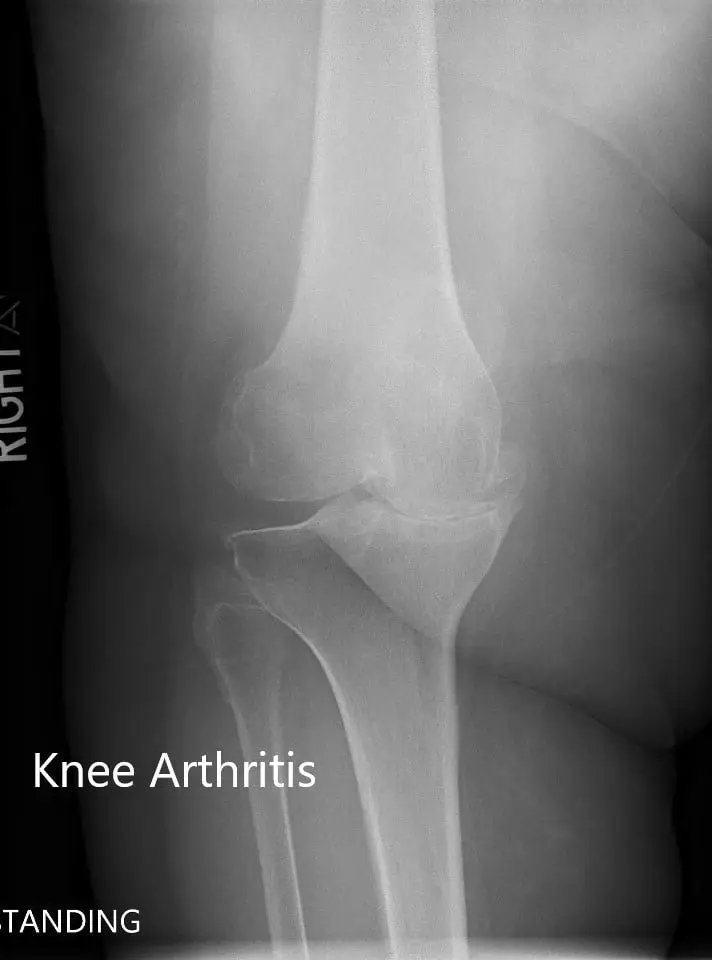

There was no distal neurological deficit. The distal extremity pulses were palpable and comparable. Imaging revealed severe tricompartmental osteoarthritis of the right knee. Options discussed with her at length including surgical and nonsurgical methods. She was given the option of right custom knee replacement. She agreed to go ahead with it.

Preoperative X-ray of the right knee showing AP and lateral views.